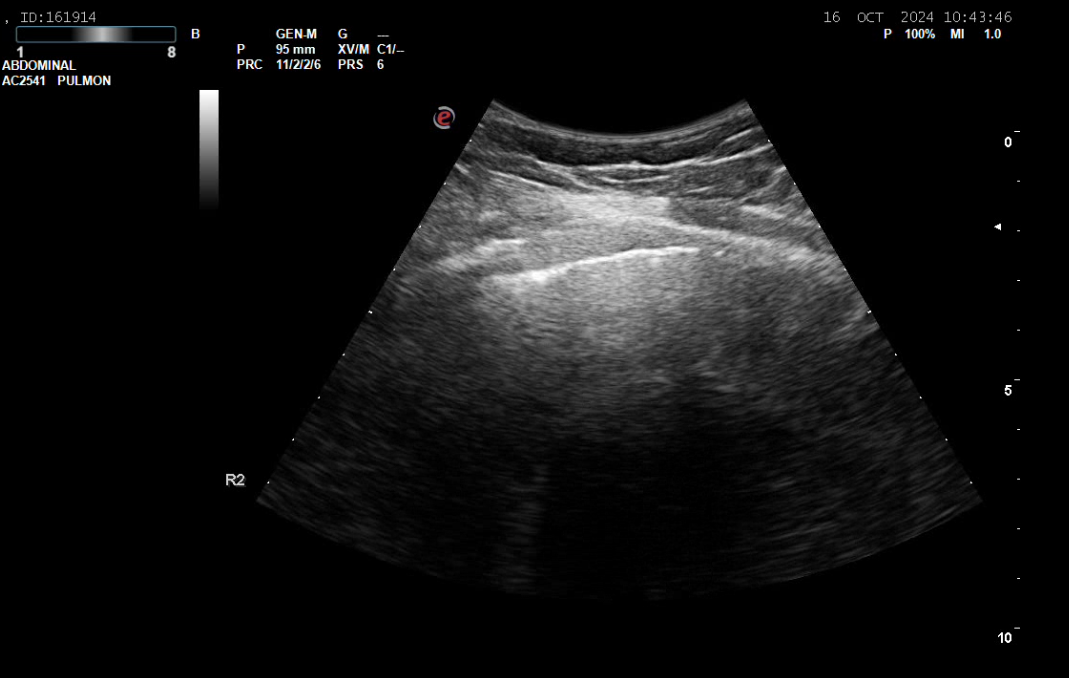

La eco a pié de cama muestra masa/atelectasia LID.